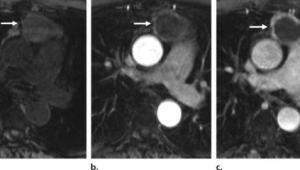

在众多的胸部检查方法中,胸部CT检查具有独特的优势。胸部CT能够清晰地显示胸部的组织结构,包括肺部、纵隔、胸膜等部位,对于早期发现微小的肿瘤病灶具有很高的灵敏度。与传统的胸部X光检查相比,胸部CT能够提供更详细的图像信息,有助于医生更准确地判断病变的性质和位置。而且,随着医学技术的不断进步,现在的胸部CT检查辐射剂量已经大大降低,对人体的影响也在可接受的范围内。